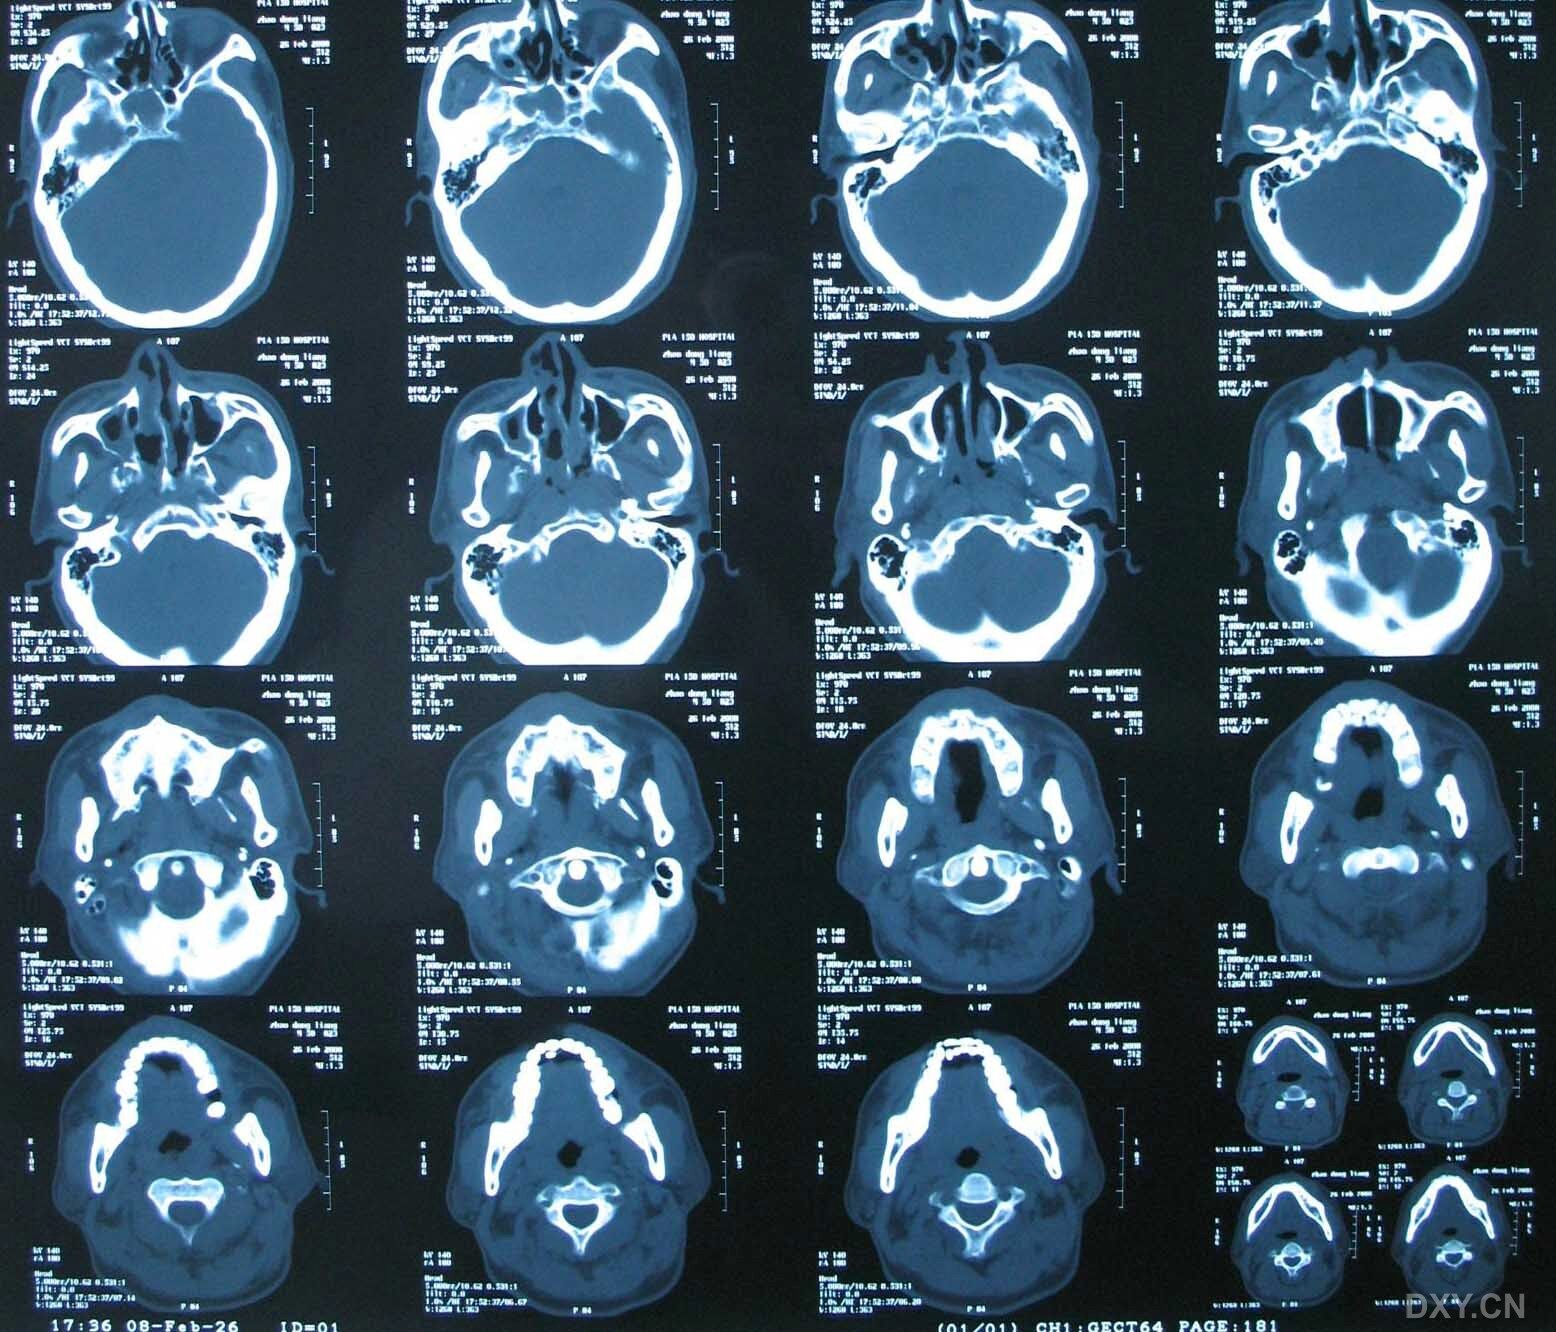

【病例讨论】上颌骨骨折何以引起张口受限 [病例帖]

【急诊】颧骨骨折,上颌骨骨折ct表现

上颌骨骨折

上颌骨骨折 [病例帖]